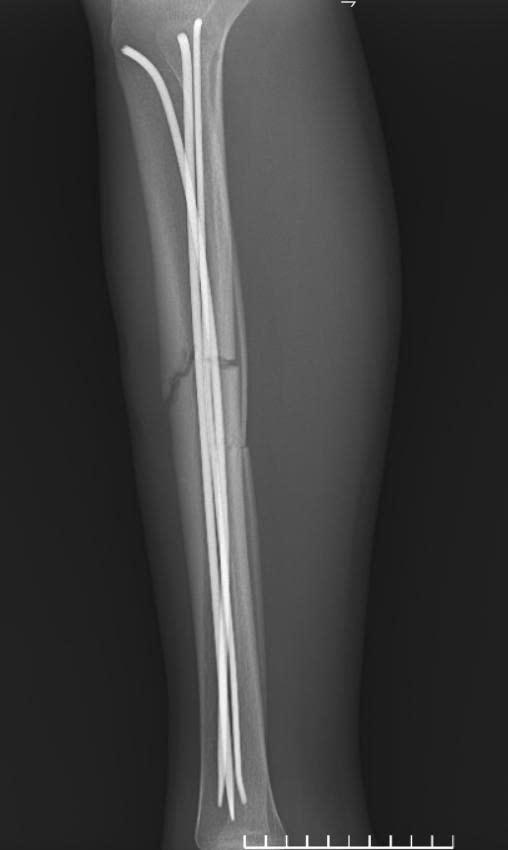

Sau hội chẩn chuyên môn, người bệnh được chỉ định phẫu thuật kết hợp xương dưới hướng dẫn của hệ thống màn hình tăng sáng (C-arm). Đây là thiết bị hiện đại hỗ trợ bác sĩ quan sát rõ vị trí ổ gãy trong suốt quá trình phẫu thuật, giúp nắn chỉnh xương về đúng trục giải phẫu và đặt dụng cụ cố định xương một cách chính xác, hạn chế tối đa sang chấn cho người bệnh.

Ca phẫu thuật được tiến hành ngay trong đêm và diễn ra thuận lợi. Các bác sĩ đã cố định vững chắc ổ gãy, xử trí tốt phần mềm và vết thương hở, tạo điều kiện thuận lợi cho quá trình liền xương và phục hồi chức năng vận động. Sau 6 ngày điều trị, tình trạng người bệnh ổn định và được xuất viện theo đúng dự kiến.